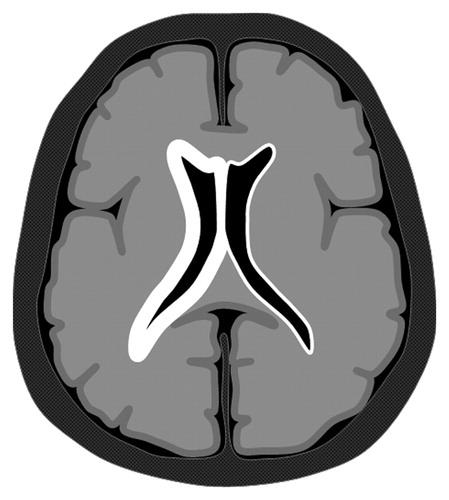

(а) На рисунке аксиального среза изображен разрыв абсцесса правой лобной доли в желудочковую систему, что явилось причиной вентрикулита. Обратите внимание на характерный уровень осажденного детрита в желудочках и воспалительные изменения по ходу стенок желудочков.

(б) MPT, FLAIR, аксиальный срез: определяется очень высокая интенсивность сигнала по ходу эпендимы желудочков в сочетании с заполняющим преддверия боковых желудочков гиперинтенсивным детритом. FLAIR и ДВИ являются наиболее чувствительными последовательностями в диагностике вентрикулита. Обратите внимание на абсцесс, локализованный в базальных ганглиях справа.